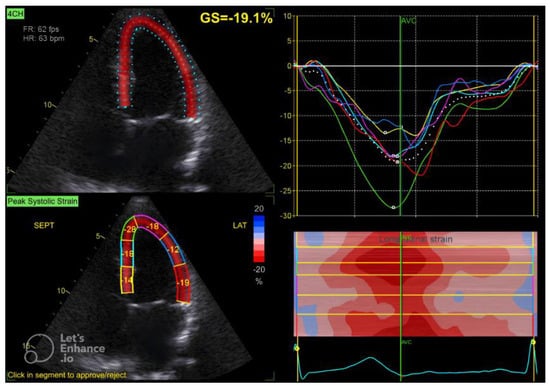

2.2. Echocardiographic Assessment

| GLS (%) | −20.25 ± 2.53 |